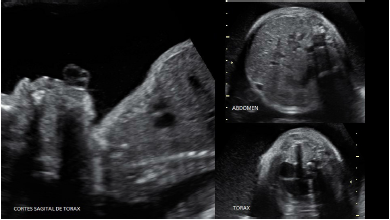

Se presenta el caso de una primigesta de 20 años de edad con 30 semanas de edad gestacional por ecografía precoz. Acudió al servicio de ecografía con diagnóstico de acondroplasia fetal, sin antecedentes personales ni familiares de importancia con relación a patologías de orden genético. Al examen ultrasonográfico se halló ponderado fetal de 2 323 g (p12 para la EG), fémur corto (p< 2DE) y curvo, tórax estrecho (circunferencia de 172 mm cortas, abdomen protuberante, macrocefalia DBP de 93 mm (>p 97,7%) CC de 319 mm (>p 97,7%), con cráneo en forma de trébol, frente prominente y aplanamiento nasal; relación fémur-pie de 0,4 (figuras 1 y 2). Otro hallazgo fue la presencia de polihidramnios leve (pozo mayor de 8,1 cm). No se encontraron malformaciones cardiacas. La reconstrucción 3D evidenció el acortamiento de los miembros superiores e inferiores y las características faciales (figura 3). De acuerdo a los hallazgos, se planteó el diagnóstico de TD, informando a la familia acerca del grave pronóstico del feto. El parto vaginal se dio una semana después, con un recién nacido vivo de sexo masculino de 2 015 g, Ápgar 2 al minuto y 5 a los 5 minutos, requiriendo intubación endotraqueal y soporte ventilatorio. Fue hospitalizado en UCI neonatal con el diagnóstico de insuficiencia respiratoria. El estudio radiográfico evidenció costillas acortadas, con los huesos largos de los miembros superiores e inferiores cortos y curvos (figura 4). El neonato falleció por insuficiencia respiratoria a los 7 días.

Se continúa con el estudio del cráneo fetal, evaluando la forma, tamaño de la cabeza y grado de mineralización; no se debe olvidar que muchas DE muestran macrocrania o deformaciones(6,7). Estas deformaciones del cráneo se producen por cierres prematuros de las suturas (craneo- sinostosis)(9); una de las más características es el cráneo en trébol, que en el caso se presentó pero como un fenotipo muy leve. La evaluación de la cara fetal debe ser completa, iniciando con el perfil fetal en busca de frente prominente, aplanamiento nasal o micrognatia; luego, se descarta lesiones de la línea media y defectos oculares (hipo o hipertelorismo)(10); característicamente, en la TD se observa frente prominente y aplanamiento nasal, como se observa en la figura 3. El siguiente paso sería la evaluación de la columna fetal, para descartar problemas de escoliosis, hemivértebras, deficiente mineralización o defectos del tubo neural(6,7,8).

Es imprescindible realizar una neurosonografía completa en todos los casos, por la asociación con defectos neurológicos. Los casos de TD se suelen asociar a malformaciones corticales del lóbulo temporal(11). La ecocardiografía fetal es también mandatoria; el hallazgo de cardiopatías ayuda a estrechar aún más las posibilidades diagnósticas y establecer pronóstico(6,7,8).